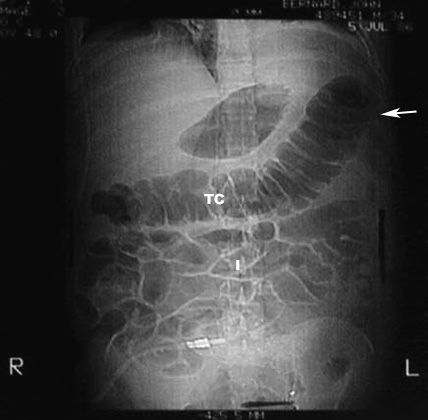

Cut off sign and Ileus

• White arrowpoints to Transeverse colon cut off at Splenic flexure. No air in descending colon.

• TC: Transverse colon

• I: Represents small bowel loops with air suggestive of Ileus